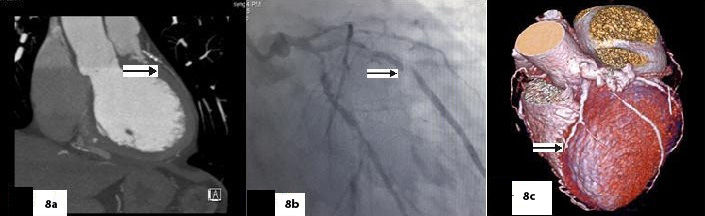

Five patients (12.5 %) had normal angiograms [Table/Fig-2,2b,3,3b], six (15%) had non-significant disease [Table/Fig-4,4b,5a,5b] and 29 patients (72.5%, 26 male & 3 female) had significant disease [Table/Fig-6a,6b],[7a,7band8] on CT coronary angiography, which was also proved on invasive angiography [Table/Fig-9]. The incidence of significant coronary detected was highest in age group of 41-60 years [Table/Fig-10].

(Sagittal), (Axial), (VRT) images & catheter angiography image showing significant stenosis in mid LAD